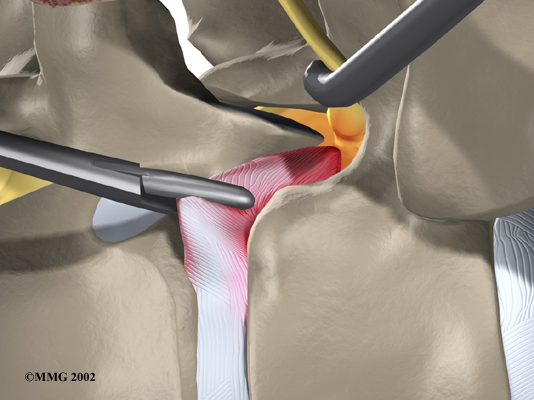

Video Assisted Thoracoscopy Surgery (VATS)

Recent developments in thoracic surgery include video assisted thoracoscopy surgery (VATS). This procedure is done with a thoracoscope, a tiny television camera that can be inserted into the side of the thorax through a small incision. The camera allows the surgeon to see the area where he or she is working on a . Small incisions give passage for other instruments used during the surgery. The surgeon watches the TV screen while damaged portions of the disc.

Categorized as minimally invasive surgery, VATS is thought to be less taxing on patients. Advocates also believe that this type of surgery is easier to perform, prevents scarring around the nerves and joints, and helps patients recover more quickly.